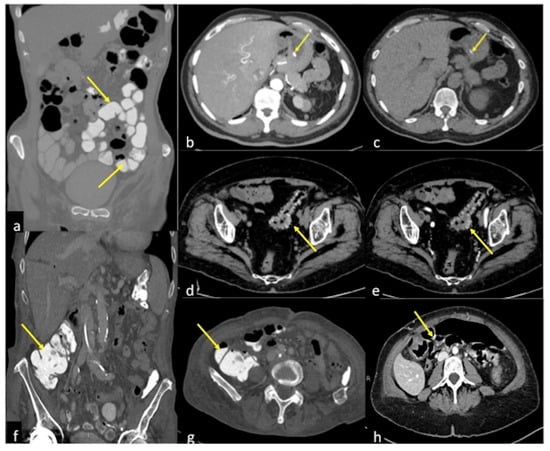

| Diverticulosis (Figure 33) | Asymptomatic or bleeding. | Protruding sacs where the vessels pass through the muscularis layer, between the mesenteric and antimesenteric taenia. |

| Angiodysplasia (Figure 5 and Figure 34) | Asymptomatic or bleeding. | Small hyperdense nodules within the intestinal wall, best defined in the portal phase of the study. |

| Rectal Varices and Haemorrhoids (Figure 35) | Pain and/or bleeding. | Dilated veins with possible bleeding visible in the portal phase; rectal varices are located proximal to the linea dentata while haemorrhoids are located in the anus. |

| Colorectal Cancer/Polyps (Figure 6, Figure 36, Figure 37 and Figure 38) | Bowel obstruction with or without bleeding. | Adenocarcinoma: irregular wall thickening with or without stenosis [25]; Polyps: mass-forming protrusions in the intestinal lumen with vascularised peduncle. |

| Inflammatory Bowel Disease (Figure 39 and Figure 40) | Haematochezia-rectorrhagia. | Acute: thickening of the walls, engorgement of the adjacent vasa recta, hyperaemia of the mucosa and infiltration of perirectal fat. Chronic: the colon and rectum are narrowed and shortened, without haustra, and with proliferation of the perirectal fat. |

| Colitis (Figure 41) | It depends on the aetiology. | Non-specific but associated with medical history, the clinical history and location of the lesions, it may be useful for diagnostic purposes. |